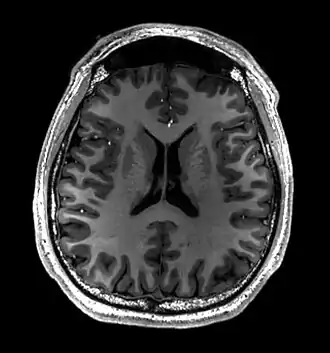

Cross-sectional T1-weighted MRI of a healthy human brain acquired with an ultra high-field MR of 7 Tesla field strength